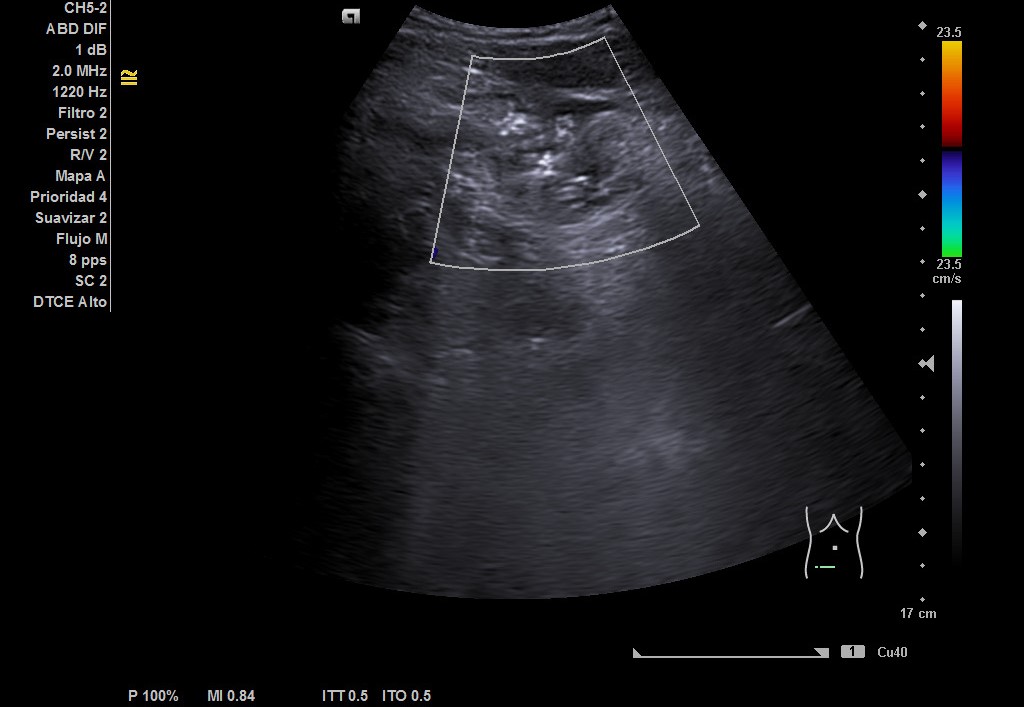

Hígado de tamaño, forma y ecoestructura conservadas, con parénquima homogéneo. Vena porta de calibre conservado.  Ausencia de signos de dilatación de la vía intra o extrahepática. Vesícula biliar de paredes finas, sin contenido ecogénico en su interior. Páncreas de características normales. Riñones de tamaño y localización conservada, sin hidronefrosis. En FID imagen heterogénea delimitada, de 50x30 mm, con posible edema de pared y focos ecogénicos en su interior.

Complicaciones post-quirúrgicas (Plastrón inflamatorio vs absceso). Diagnóstico diferencial: Diverticulitis colon derecho. Tras ecografía realizada por Radiología en el servicio de Urgencias y valoración por Cirugía General se llegó al diagnóstico de plastrón inflamatorio y colección postapendicectomía.